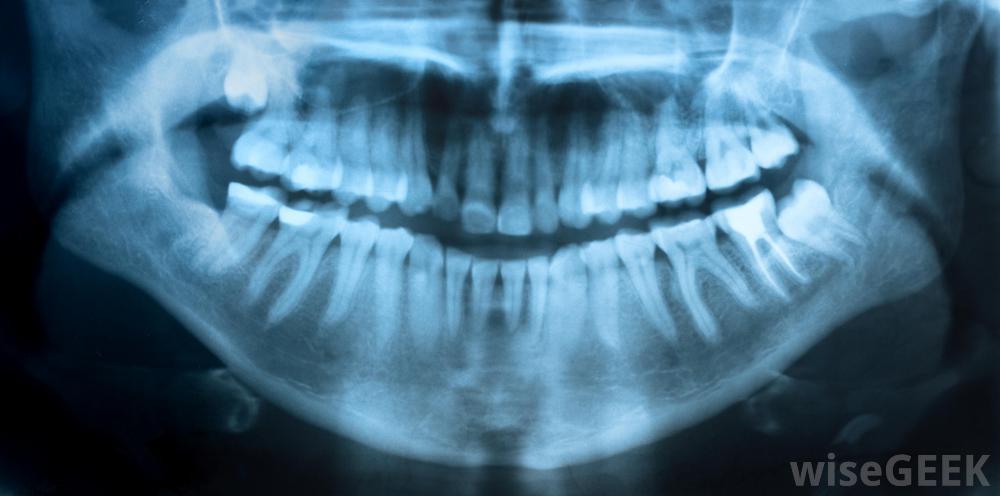

可能需要牙科x光片来评估错牙合。牙医通常会识别出三种不同的类型或类别的错牙合情况。最常见的类型是I级。I级是轻度上齿略高于下牙的错牙合。I类患者的咬合仍然正常。

正畸医生可能会使用固定器来纠正不正确的下颌对齐有这种情况的病人通常在正常的牙科检查中被诊断出来。牙医会要求病人咬紧牙关检查牙齿的排列情况。他也可以照x光片。如果他怀疑有问题,牙医通常会送病人去看正畸医生